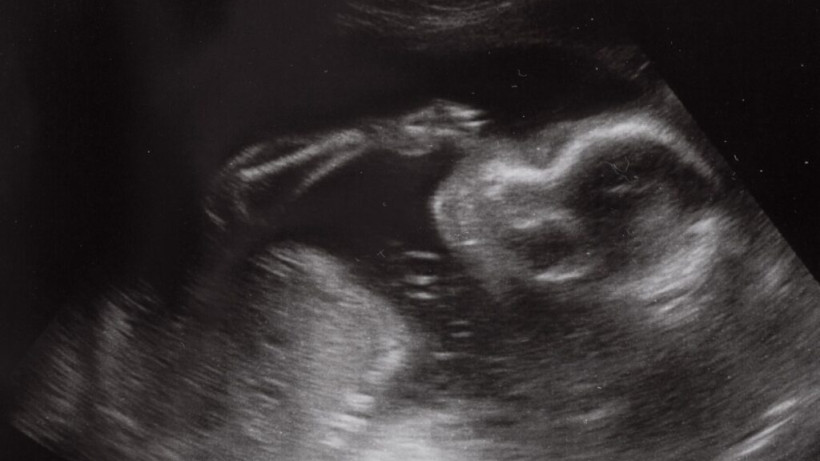

Biorę na ręce i już kocham

– Każdemu prowadzę zeszycik – nazywam go księgą życia – w którym zapisuję wszystko od początku. Jak się dziecko wychowywało, jak jadło. Po kolei opisuję etapy rozwoju

Nauka w służbie płodności – naprotechnologia

Z lek. Darią Mikułą-Wesołowską, dyrektorem Ogólnopolskiego Ośrodka Troski o Płodność, o odkrywaniu tajemnic ludzkiej płodności, trudnościach w poczęciu dziecka i holistycznym podejściu do człowieka,